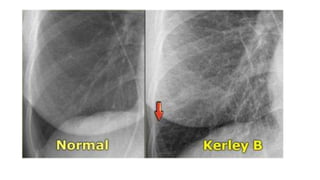

This document provides an overview of heart failure. It begins by outlining the objectives of understanding pathophysiology, classification, therapeutic targets, and initiating guideline directed medical therapy. It then discusses the anatomy, myocardial mechanics, effects on physiology, and introduction to heart failure. Classification systems such as ESC and AHA/ACC are presented. The document discusses heart failure in India, hospitalization risk, definition, and why ejection fraction is used for classification. It covers the pathophysiology, signs and symptoms, assessment, biomarkers, ECG, CXR findings, echocardiogram evaluation, treatment approaches for acute and chronic heart failure, guideline directed medical therapies including drugs, and SGLT2 inhibitors.